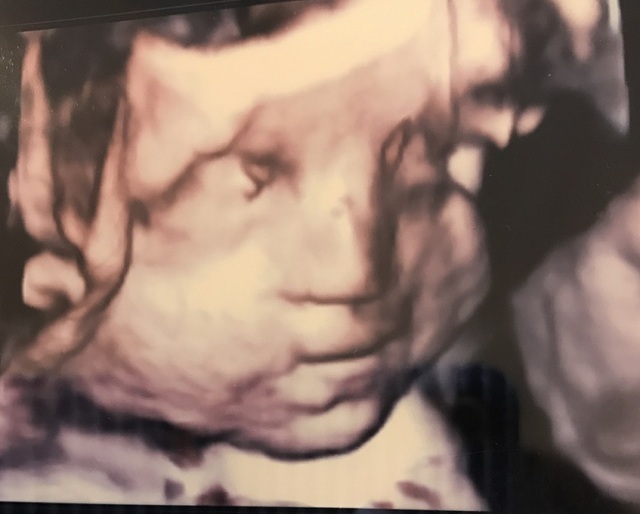

21週0日(21w0d・男の子)|ゆいぷる さん(31歳)

エコー写真撮影時のエピソード:

こんなにはっきりした赤ちゃんのエコー写真ある⁉️と夫婦でびっくりしました。 どっかの銅像でありそうだよね!と笑いながら話しました。

この顔、旦那さんにそっくりで、俺似だ!とすごくうれしそうに話してたのを思い出しました。